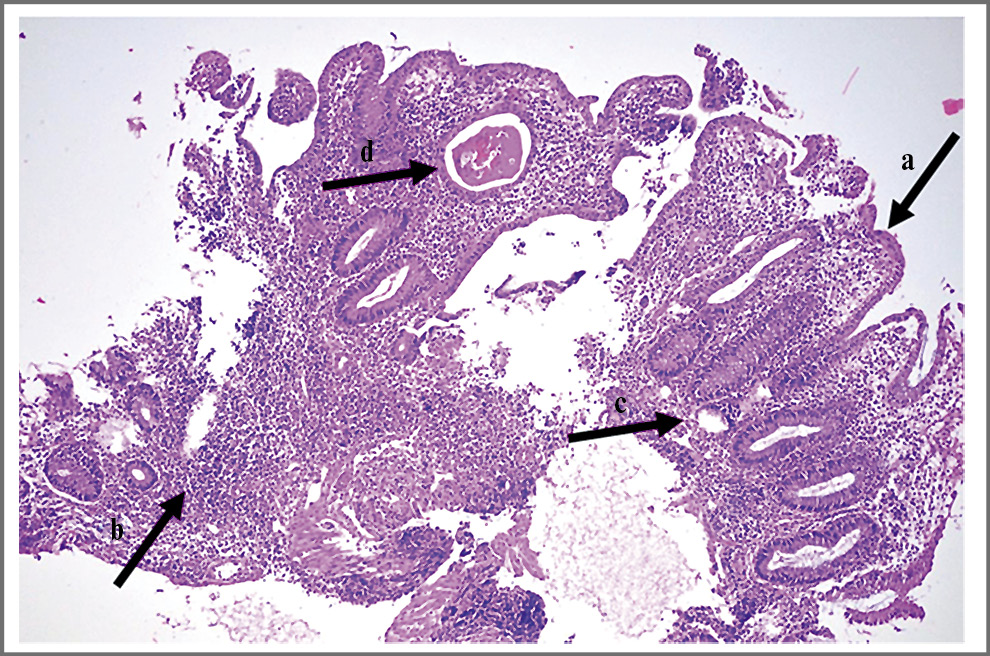

Анализы крови: Нb – 108 г/л, эритроциты – 4,21×1012/л, гематокрит – 33,3%, MCV – 79 фл, MCH – 25,7 пг, тромбоциты – 478×109/л, лейкоциты – 15,1×109/л, нейтрофилы – 75,7%, лимфоциты – 10,6%, моноциты – 11,9%, эозинофилы – 1,0%, базофилы – 0,8%; СРБ – 172,83 мг/л, фибриноген – 7,56 г/л, РСТ – 0,5 нг/мл, общий белок – 43,1 г/л. Посев содержимого абсцесса носовой перегородки: рост Staphylococcuc epidermidis в низком титре (по-видимому, контаминация материала при заборе пробы). Рентгенография придаточных пазух носа: лобные/гайморовы пазухи носа прозрачны. Видеоколоноскопия: слизистая оболочка в доступных осмотру отделах гиперемирована, отечна, с зернистой поверхностью, множественными эрозиями, покрытыми фибрином, вязкой слизью. Отмечается контактная кровоточивость. Выполнена биопсия. Заключение: эндоскопическая картина ЯК средней степени активности. Гистологическое заключение (рис. 4, 5): фрагменты слизистой оболочки толстой кишки с очаговым некрозом поверхностного эпителия и инфильтрацией соединительнотканной стромы до собственной пластинки лимфоцитами, плазматическими клетками в умеренном количестве, местами с участками формирования небольших лимфоидных фолликулов.

Рис. 5. Фрагмент слизистой оболочки толстой кишки с очаговым некрозом поверхностного эпителия. Покровный эпителий частично представлен незрелыми регенерирующими эпителиоцитами, лишенными муцина (a). Плотный инфильтрат, состоящий из лимфоцитов и плазматических клеток, нейтрофильных лейкоцитов в пределах слизистой оболочки (b) и поверхностных отделах подслизистого слоя; наличие небольших эрозий меду криптами (c). Железы с кистозным расширением (d) и наличием в просвете гомогенного содержимого с примесью лейкоцитов; формирование крипт-абсцессов. Окраска гематоксилином и эозином ×200.